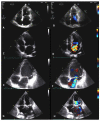

Valvular heart disease is a leading cause of cardiovascular morbidity and mortality and a major contributor of symptoms and functional disability. Knowledge of valvular heart disease epidemiology and a deep comprehension of the geographical and temporal trends are crucial for clinical advances and the formulation of effective health policy for primary and secondary prevention. This review mainly focuses on the epidemiology of primary (organic, related to the valve itself) valvular disease and its management, especially emphasizing the importance of heart valve centers in ensuring the best care of patients through a multidisciplinary team.